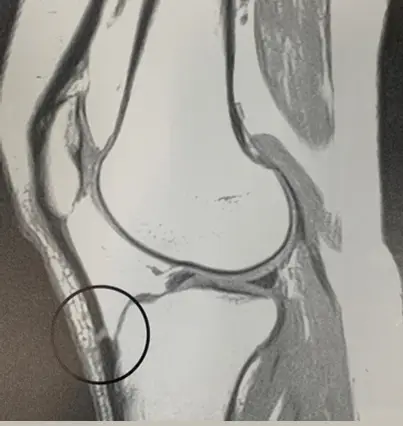

下圖是下肢磁振造影影像,其中之圓形影像為下列何者所造成?

- 影像切面:這是一張膝關節的矢狀面(sagittal view)磁振造影影像。

- 解剖構造:黑色圓圈標示的區域為「髕骨肌腱(patellar tendon)」,連接髕骨下緣與脛骨粗隆。

- 異常表現:正常情況下,肌腱由於含有高度排列的膠原纖維,其 T2 弛緩時間(T2 relaxation time)極短,因此在常規的 MRI 脈衝序列中均應呈現均勻的低訊號(黑色)。然而,在圓圈標示處的肌腱內部,卻出現了局部的中高訊號(偏灰白)。

- 臨床推論:此病灶呈現平滑的訊號改變,且未見肌腱明顯增厚或周邊水腫等真實病理變化(如肌腱炎或撕裂傷)。在標準圓筒狀超導體 MRI 掃描儀中,主磁場(B0)方向平行於病患的長軸(Z軸)。當膝關節微彎或肌腱本身的自然走向與主磁場 B0 呈現約 55 度角時,極易在此處觀察到訊號異常升高,這正是魔角假影的典型表現。

正確答案為 D。 圖中標示的部位為髕骨肌腱。由於該段肌腱的解剖走向相對於主磁場(B0)剛好形成約 55 度的夾角,觸發了魔角效應。偶極交互作用的減少使得該區域的 T2 弛緩時間變長,在短 TE 的造影參數下便會呈現出局部的明亮訊號。這種現象在骨關節 MRI 中十分常見,特別是在髕骨肌腱、阿基里斯腱(Achilles tendon)以及肩關節的棘上肌肌腱(supraspinatus tendon)。